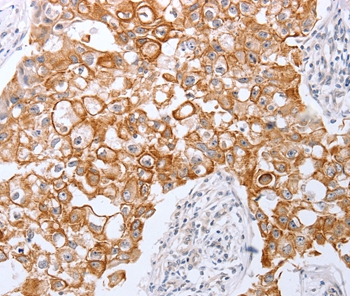

Immunohistochemical analysis of paraffin-embedded Human breast cancer tissue using #35962 at dilution 1/25.

Immunohistochemical analysis of paraffin-embedded Human cervical cancer tissue using #35962 at dilution 1/25.